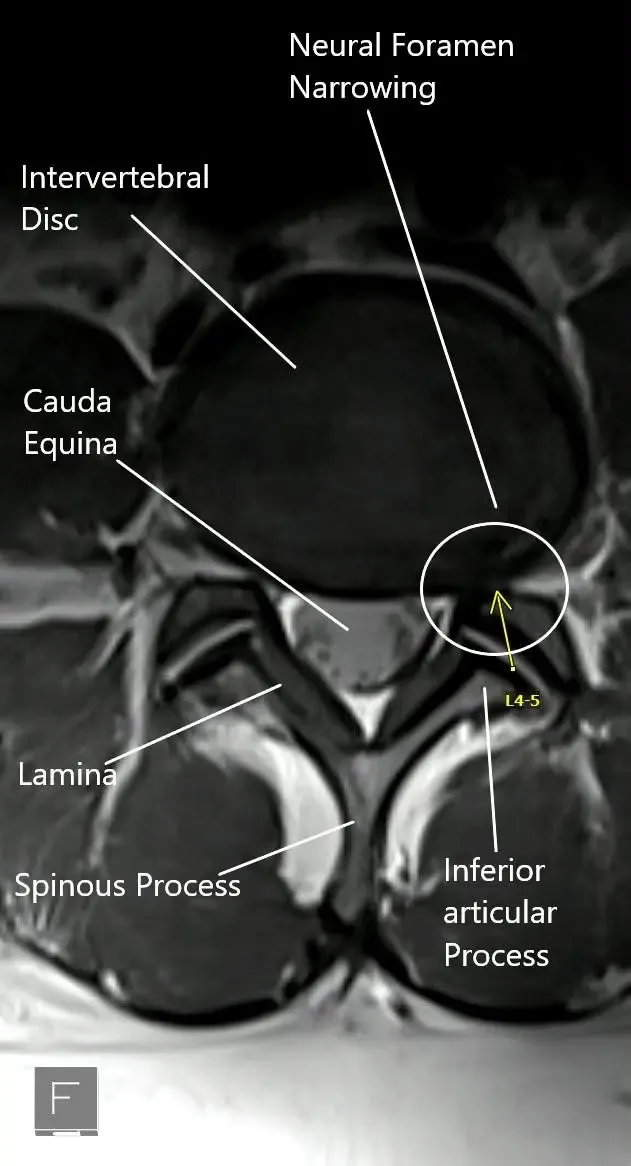

MRI showing the axial section of the lumbar spine with neural foramen narrowing.

The dural sac containing all the nerve roots from cauda equina lie inside the central canal. The central canal is bound by the vertebral body and the intervening intervertebral disc in the front and the lamina in the back. The facet joints are present near the neural foramen on the sides of the vertebral canal.